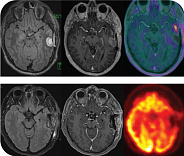

Исследовательская группа врачей клиники «Европейский медицинский центр» разработала и запатентовала инновационный подход к лечению заболевания c использованием баллонной электронной брахитерапии, которая уничтожает остаточные фрагменты злокачественного новообразования, ответственные за быстрый рецидив. Новый метод направлен на продление продолжительности и улучшения качества жизни пациента без прогрессирования.

Эта методика уже показала свою эффективность при терапии рецидивов опухоли головного мозга. Теперь специалисты намерены подтвердить результаты на первично диагностированном заболевании.